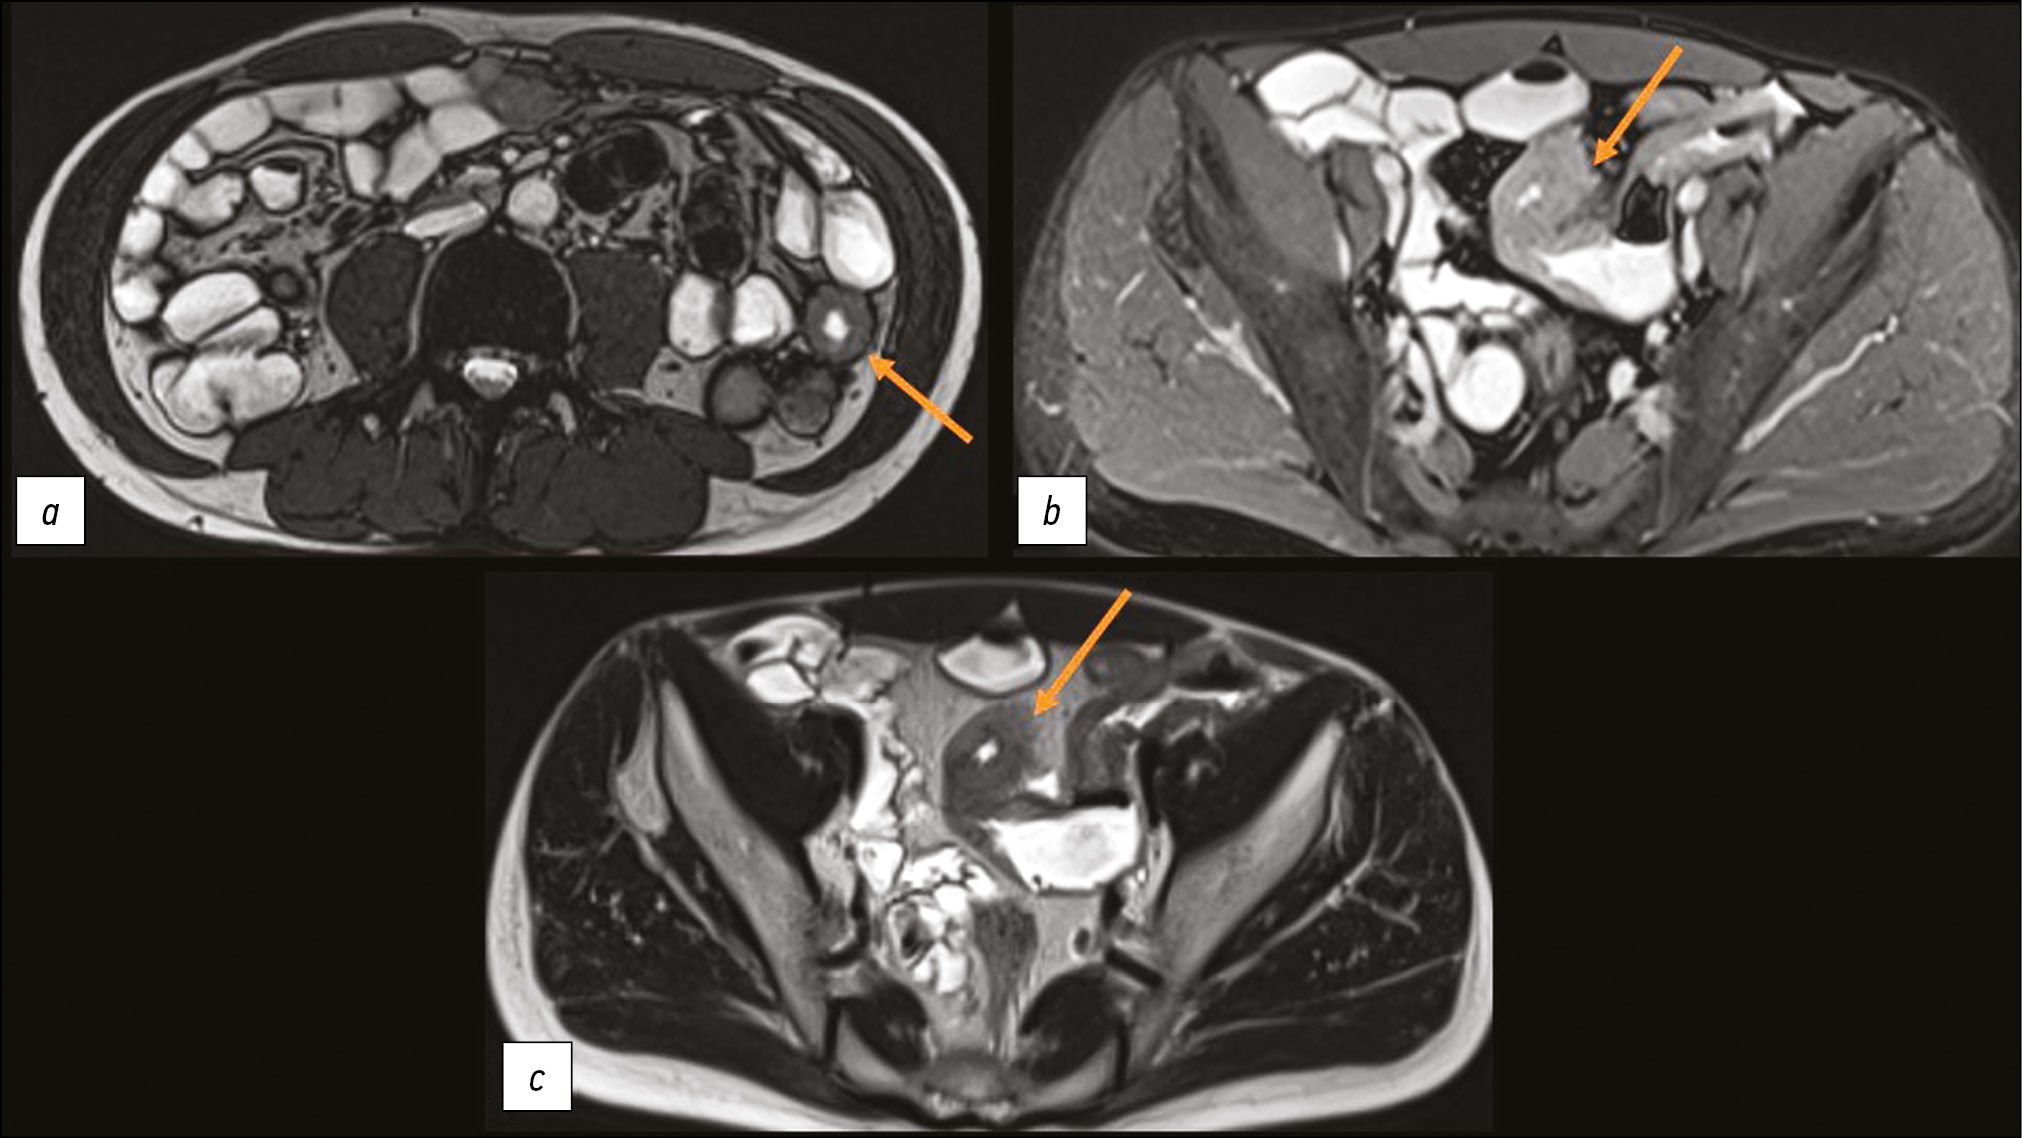

To determine the extent and volume of the lesion, MR enterography was performed after administering 1.2 L of mannitol solution orally. Four local areas of uneven wall thickening were noted in the small intestine: thickening of up to 8 mm over 25 mm with narrowing of the lumen to 5 mm, thickening of up to 12 mm over ~90 mm with narrowing of the lumen to 3 mm, thickening of up to 10 mm over 160 mm with narrowing of the lumen to 3 mm, and thickening of up to 9 mm over ~32 mm with narrowing of the lumen to 3 mm (Figs. 2 and 3). These areas of the small intestine actively accumulated the contrast agent and showed signs of limited diffusion on diffusion-weighted imaging. Because the lesions resembled those seen in intestinal tuberculosis, an immunodiagnosis of tuberculosis infection (interferon gamma release assays, T-SPOT.TB, with a negative result) and chest MSCT (with no pathology) were performed.

Fig. 2. Magnetic resonance enterography, axial plane: the arrows show thickened areas of the small intestine.